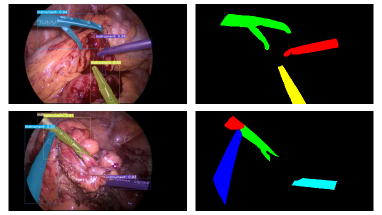

Notably, our top model produces high-quality and temporally consistent masks. Figure 4 shows some examples with varying types and number of instruments together with their respective ground truth annotations. The model is robust to occluded instruments and various harsh conditions, like blood, smoke, and poor lighting. Nevertheless, it struggles with transparent instruments and small instruments on the edge of the field of view. Figure 5 illustrates some examples of challenging frames for our proposed algorithm, which we will seek to address in future work.